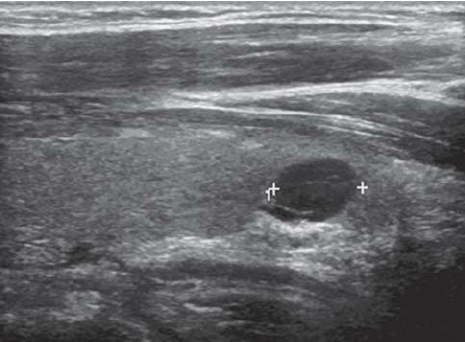

고형(solid): 초음파를 보면 액체 여부를 어느 정도 구별할 수 있는데 딱딱하게 보이는 구조물을 말합니다. 아래 사진은 알아보기 쉽게 액체와 고체부분이 섞여있는것을 가지고있는데요, 검은부분이 액체이고 그안에 밝은부분이 고체부분입니다.

저에코(hypoechogenic n odule) : 초음파에서 다른 조직에 비해 더 어두워 보이는 병변을 말합니다.